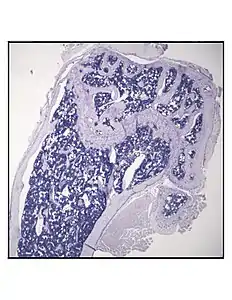

Representative distal femur histologic section of a 16-week-old C57BL/6 mouse after 6 weeks of calorie restriction demonstrating an increased quantity of marrow adipocytes.

In order to understand the physiology of BMAT, various analytic methods have been applied. BMAds are difficult to isolate and quantify because they are interspersed with bony and hematopoietic elements. Until recently, qualitative measurements of BMAT have relied on bone histology,[51][52] which is subject to site selection bias and cannot adequately quantify the volume of fat in the marrow. Nevertheless, histological techniques and fixation make possible visualization of BMAT, quantification of BMAd size, and BMAT's association with the surrounding endosteum, milieu of cells, and secreted factors.[53][54][55]